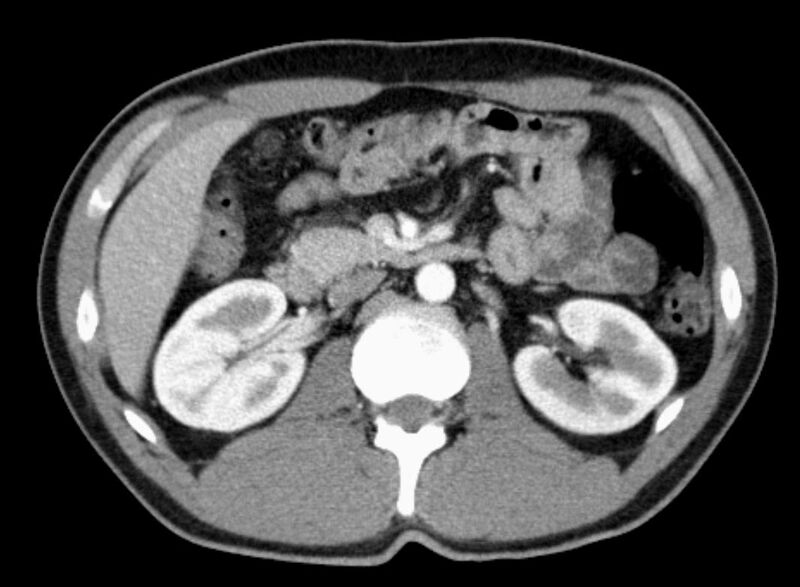

Abdomen (Bauch und Becken)

• Diagnostik von entzündlichen und tumorösen Erkrankungen der Bauchorgane

• Diagnostik von akuten Notfällen wie Darmverschluss, Hohlorganperforation oder Traumafolgen

• Darstellung der großen Gefäße zur Erkennung von Gefäßverschlüssen (z. B. Mesenterial - Arterienembolie oder Einengungen von Gefäßen (z. B. Nierenarterien)

• Darstellung und Therapieplanung von Aneurysmen (CT- Angiographie)